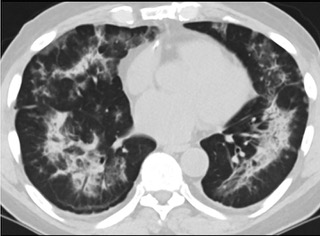

疑點一,電子煙患者的CT影像和臨床表現(xiàn)并不具有特異性。所謂美國電子肺炎患者,其實是對沒有其他合理診斷證據(jù)、吸食電子煙肺炎患者的統(tǒng)稱。這些患者在病發(fā)前90天內(nèi)吸食了電子煙,尤其值得注意的是,部分患者的CT影像特征和臨床表現(xiàn)與病毒性肺炎患者極其相似。

疑點二,中國科研工作者從60篇研究論文中篩選出142位電子煙肺炎患者的250張影像圖片,邀請3位放射科權威專家,對上述全部影像圖片、相關病人臨床信息以及文獻原文進行了仔細全面研究與審查,又有了新的發(fā)現(xiàn)。

16位被文獻報道為電子煙肺炎的患者被專家判定為“病毒性感染”,即有可能是新冠肺炎的“疑診患者”,其中更有5位臨床癥狀和治療情況相對完整的患者被判定為“中度可疑”。因此在2019年美國報道的電子煙肺炎中存在病毒性感染的病例,而且不排除美國電子煙肺炎中存在新冠肺炎的可能性。